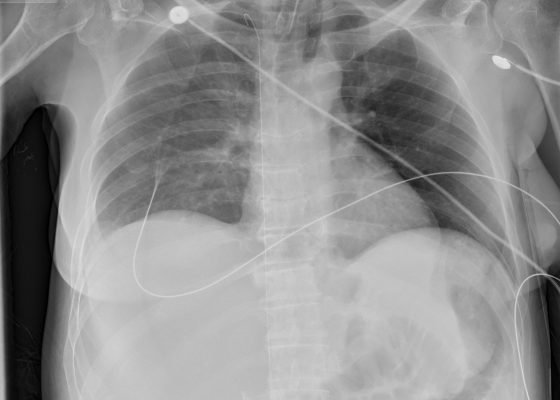

The Lost Guidewire

DOI: https://doi.org/10.21980/J82P4MInitial chest radiograph shows a guidewire in the inferior vena cava (IVC), superior vena cava (SVC), and right IJ veins.